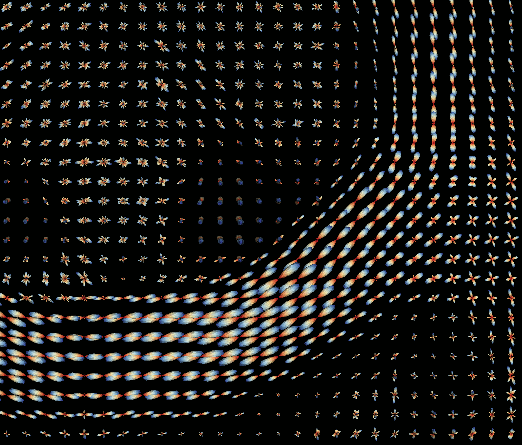

DTI and HARDI reconstruction

and metrics extraction

Streamlines reconstruction

Analysis - Reconstruction

08-10 Tensor reconstruction

11-12 fODF reconstruction

13-14 Tractographies

FA

AD

RD...

CSD PEAKS

NUFO